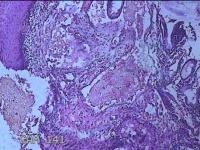

宫颈组织

性别

女

年龄

44岁

临床诊断

宫颈赘生物

一般病史

发现宫颈赘生物2年余。

标本名称

大体所见

灰白暗红色组织3.8x1.5x0.8cm一块,表面光滑,以宫颈12点缝线标记处切开,切面灰白粉红色,质软,宫颈3点处见灰白粉红色囊性肿物1.8x1.5x0.3cm一个,切开肿物,内见大量乳白色内容物,囊壁厚0.1cm。